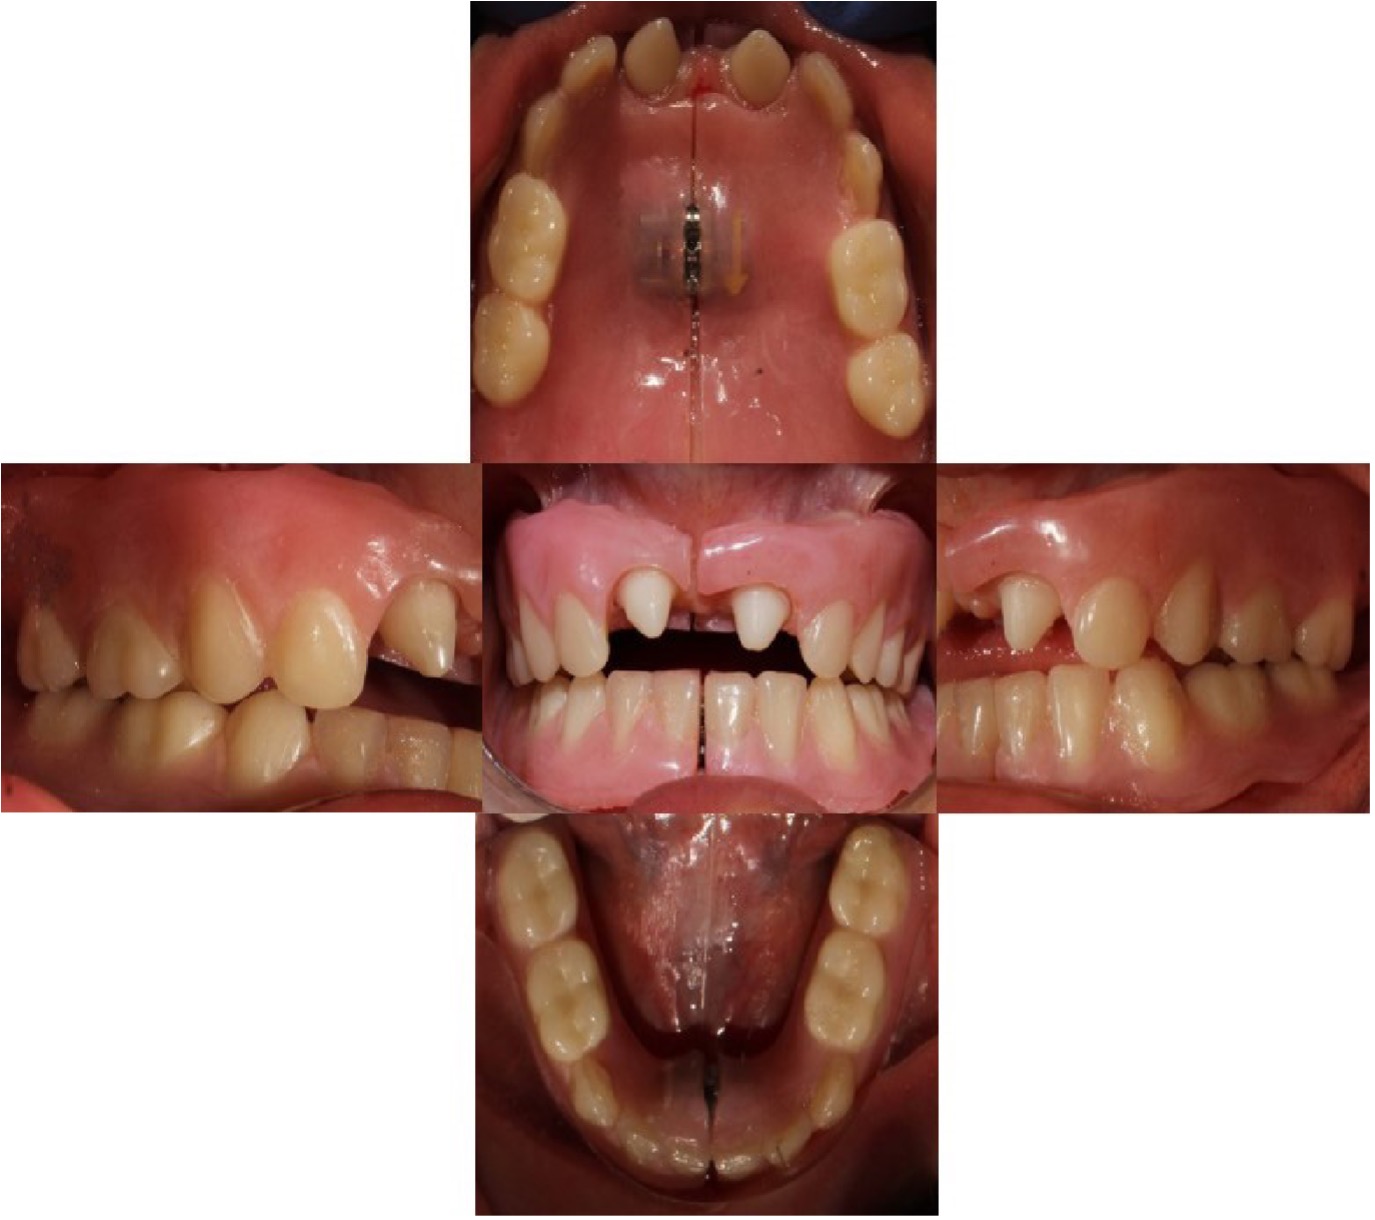

Al examen clínico general se evidenció que presenta las siguientes manifestaciones físicas generales: hipotricosis, piel seca, ausencia de cejas y pestañas, hipertelorismo, piel periorbitaria hiperpigmentada, orejas prominentes y bajas. Al examen clínico extrabucal se evidenció en las características cráneo faciales implantación baja de pabellones auriculares, depresión del tercio medio facial, tercio inferior facial disminuido, labios gruesos, resecos e hipotónicos (Figura 1).

En el examen clínico intraoral se observa Anodoncia Parcial Verdadera con presencia únicamente de los dientes 52 y 62 de forma cónica, reborde alveolar atrófico y estrecho y disminución de la dimensión vertical (Figura 2). En la ortopantomografía se observa la ausencia de todos los gérmenes dentarios permanentes con excepción de los dientes 11 y 21 en forma cónica (Figura 3) (Tabla 1).

Figura 2: Fotografías intraorales iniciales.